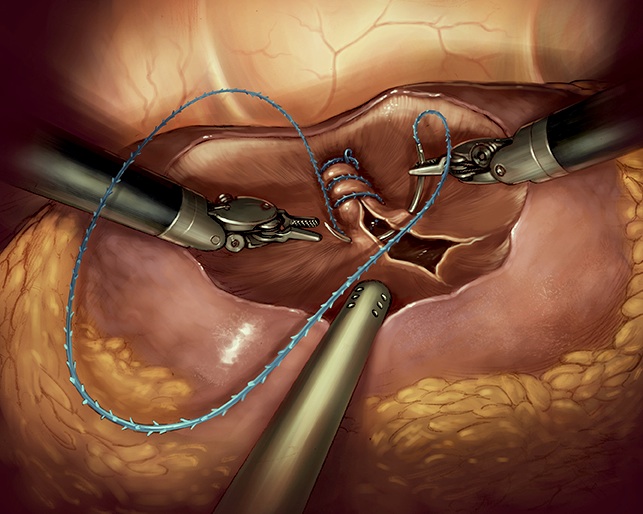

NEFRECTOMIA LAPAROSCOPICA

La cirugía convencional del riñón se hacía “a cielo abierto”, pero hoy en día en la mayoría de los centros más avanzados ha pasado a realizarse por laparoscopia. Consiste en realizar pequeñas incisiones abdominales de medio a un centímetro, por las que se introducen pinzas y tijeras especiales y una cámara que permite operar mirando una pantalla. Con esta novedosa técnica logramos la misma o mejor precisión en la curación del tumor y, al evitar las grandes incisiones de la cirugía abierta, el paciente tiene mucho menos dolor postoperatorio, y puede abandonar el hospital al día siguiente a la intervención y reincorporarse antes a su vida habitual.